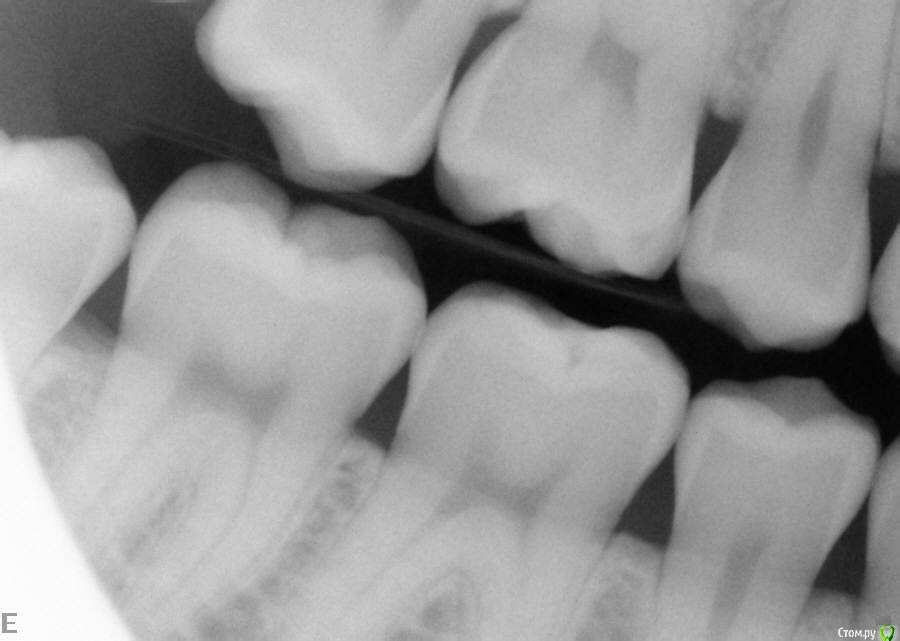

laz Опубликовано 31 мая, 2016 Поделиться Опубликовано 31 мая, 2016 Здравствуйте,Был на приеме у зубного врача, чтобы почистить зубы. Он сказал мне нужны пломбы на 4 зуба (1-7, 1-6, 2-7 2-6).Еще он сказал мне нужно удалить все зубы мудрости. (не обязательно сейчас, но в ближайщем будущем)Болей никаких у меня нет. Поэтому не знаю, как быть.Посмотрите, пожалуйста, на рентгены и очень хочу услышать Ваше мнение/совет.Заранее спасибо, Владимир. Ссылка на комментарий

red_butler Опубликовано 31 мая, 2016 Поделиться Опубликовано 31 мая, 2016 все правильно, удаляйте все восьмыеи девятый 5 Ссылка на комментарий